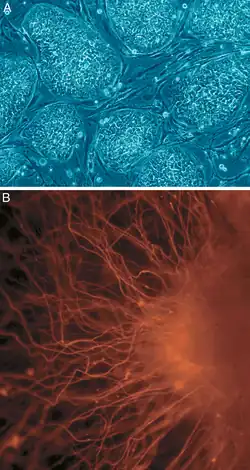

A : cellules souches humaines encore indifférenciées.

B : cellules nerveuses.

Les cellules souches adultes sont beaucoup plus rares, puisqu'une fois le développement terminé, la nécessité de proliférer peut devenir dangereuse. Les cellules souches perdurent donc en des endroits restreints dans chaque tissu ; ces niches ont des mécanismes de maintien complexes et sont régulées pour ne produire que les cellules nécessaires au maintien d'un organisme fonctionnel.

Ces cellules souches sont moins « pluripotentes » que celles constituant l'embryon : elles ne peuvent produire que des cellules spécifiques de leur tissu. Par exemple, chez les mammifères adultes, les cellules souches hématopoïétiques régénèrent en continu les cellules du sang. Il existe également des cellules souches intestinales ainsi que des cellules souches neurales. Ces dernières ne sont présentes que dans deux régions distinctes du cerveau : l'hippocampe et la zone sous-ventriculaire (zone bordant les ventricules latéraux).